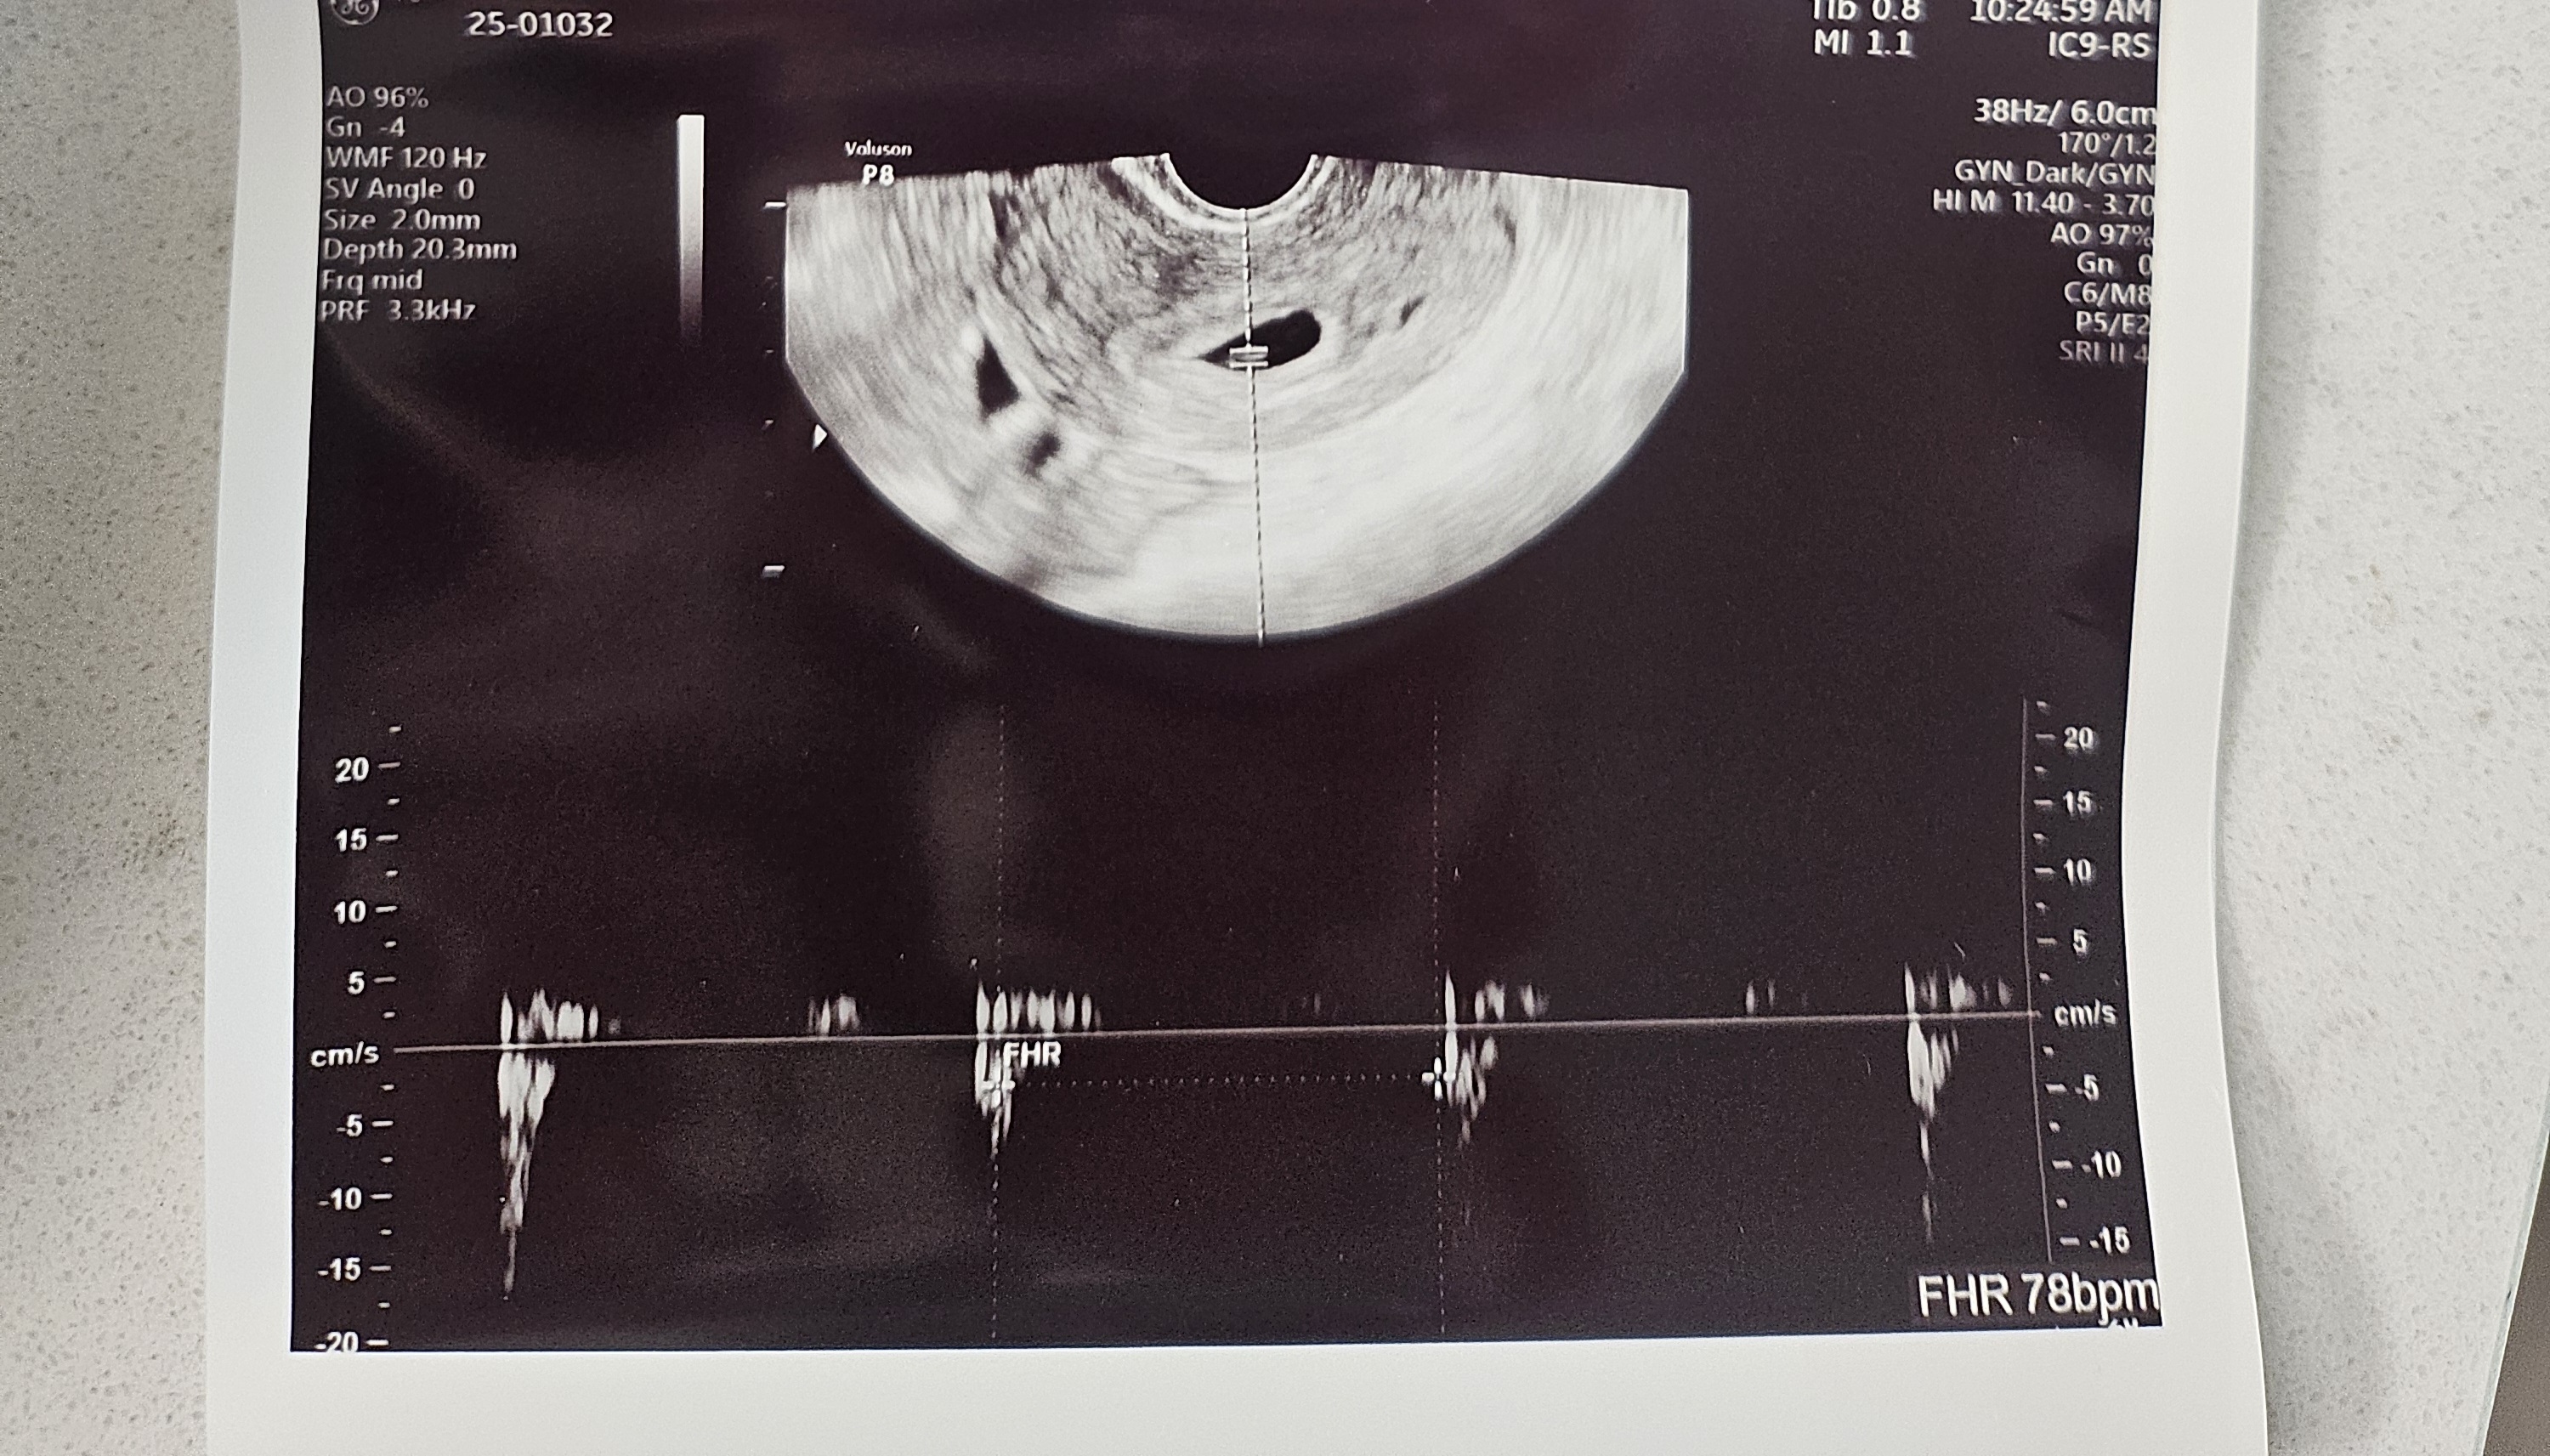

심장소리

심장소리 듣고 왔어요. 전 원래 마지막 생리가 10/19라 원래 예정일이 7/26 였다가 다시 7/30으로 밀렸다가 다시 8/4로 밀렸어요. 원래 이런게 흔한가요? 한 번 유산 경험도 있었어서 더욱 떨리네요...

막생이 10월 19일이면 주기가 길어서 배란일 추정이 어려워요. 그러면 특히나 미뤄질 수 있어서 심장소리 안정적이면 좀 안심하셔도 될 것 같아요.